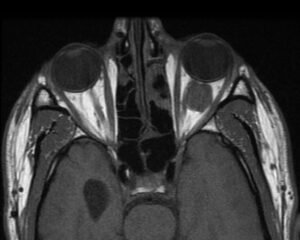

Η διάγνωση των όγκων κόγχου γίνεται αρχικά με καλή και λεπτομερή κλινική εξέταση και λήψη αναλυτικού ιατρικού ιστορικού. Παράλληλα, απαιτούνται απεικονιστικές εξετάσεις, όπως η αξονική ή/και η μαγνητική τομογραφία με χρήση σκιαγραφικού για τη λεπτομερή απεικόνιση και εξέταση των χαρακτηριστικών του όγκου, ώστε να καθοδηγήσει τον χειρουργό στη σωστή θεραπευτική προσέγγιση.